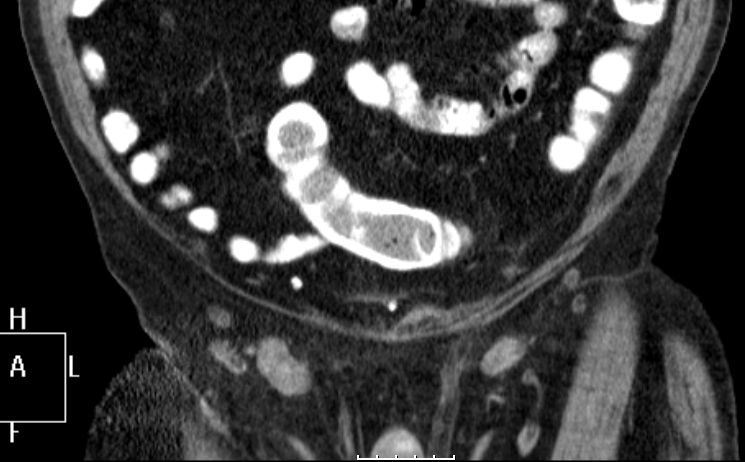

Lymphknotenmetastasen bei Peniskarzinom

95-jähriger Mann, beim vor 9 Monaten ein Plattenepithelkarzinom der Vorhaut entfernt wurde. Jetzt in beiden Leisten faustgroße, zentral zystisch zerfallende Lymphknotenpakete.